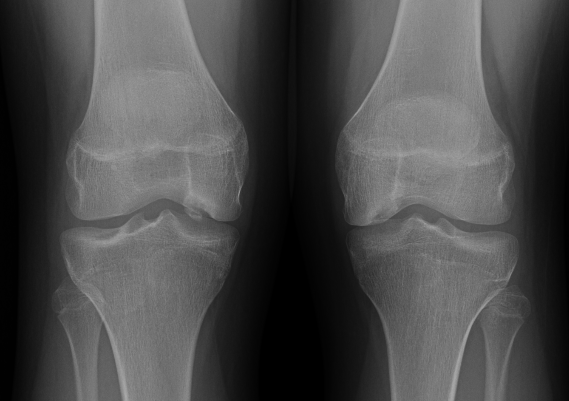

Xray classification

Stage 1: Normal / abnormal MRI

Stage 2: Lucent area of subchondral bone, can have surrounding sclerosis

Stage 3: Partial loosening

Stage 4: Completely detached / loose body

Type 2 Type 3 Type 3